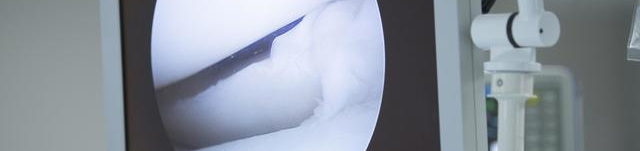

对膝、肩关节的一些病变,在明确诊断研究员后,可在镜视下用特殊器械进行手术,而取得满意效果。例如关节灌洗清创术、膝关节撕裂半月板部份或全部切除术、半月板边缘斯裂缝合术、前交叉韧带修复术、滑膜皱襞切除术、关节内粘连松解术、胫骨平台或髁间嵴骨折修整术、肩袖清创术、肱二头肌腱粘连松解术及关节内游离体摘除术等。此外,四肢大关节的类风湿性关节炎疾病可行滑膜大部切除术。